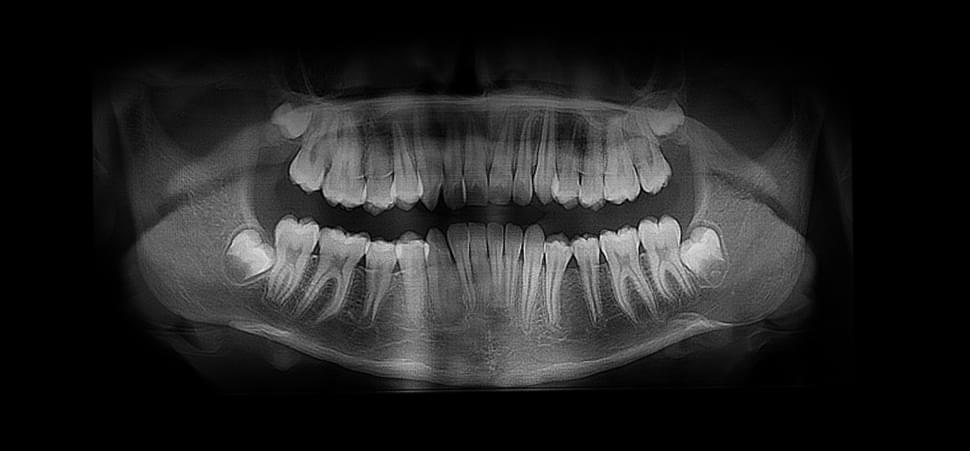

Тип знімку - 2D

Вартість - 300 грн

Загальний час прийому - 15 хв

Час сканування - 15 сек

Друк на фотопапері / e-mail / лікарю на ftp

💡 Загальна інформація:

Ортопантомограма (ОПТГ) — це як загальна "фотографія" всіх ваших зубів та щелеп на одному знімку. Це швидке і безпечне 2D-сканування, під час якого апарат робить круговий рух навколо вашої голови, щоб отримати повне зображення.

✅ Для чого використовують:

● Стоматолог бачить стан усіх зубів, одночасно на одному фото.

● Для ортодонтів (вирівнювання зубів) та перед видаленням зубів

мудрості.

● Дозволяє оцінити розвиток зубів у дітей.